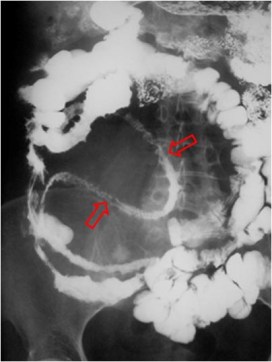

SIGNO DEL PSEUDOTUMOR

En la radiografía simple de abdomen, cuando un asa intestinal está obstruida por un vólvulo se llena de líquido y produce una falsa imagen de masa con densidad de partes blandas (flechas) que no debe confundirse con un tumor.

Este signo debe diferenciarse de las asas rellenas de líquido en la obstrucción mecánica simple. En la obstrucción en asa cerrada, la presencia del signo del pseudotumor indica que un asa intestinal se encuentra fija y permanece en la misma posición en todas las proyecciones.

En la imagen, pseudomasa causada por asas distendidas, con líquido, en la obstrucción intestinal.